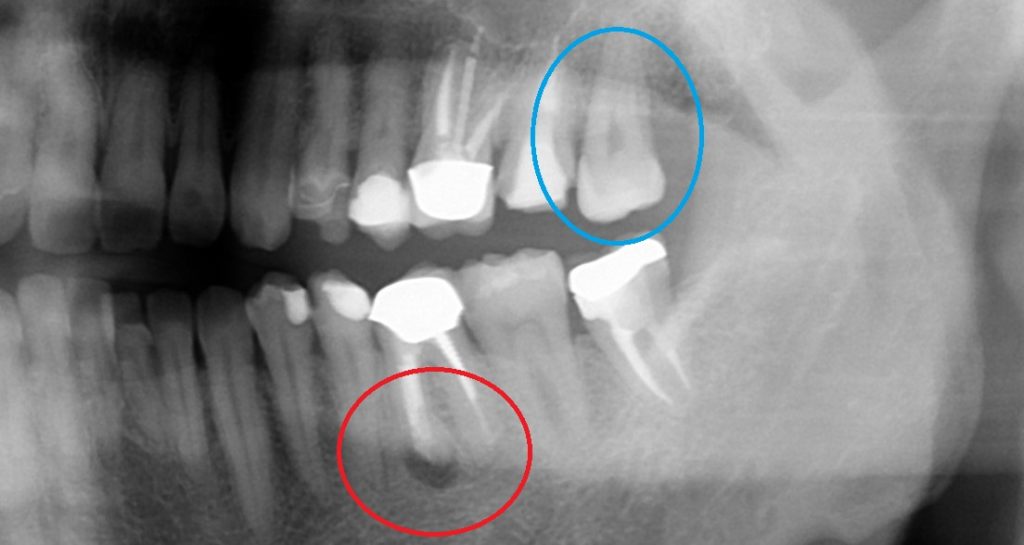

赤い丸の、左下6番目の歯です。

歯の根っこに黒い像が見えます。今回は保存が難しいので、

抜歯した後に、

青い丸の、左上の親知らずを移植します。

赤い丸の歯が、根の先が膿んで、レントゲン写真で黒くなっていました。

左下の移植、3か月後のレントゲン写真です。

まだレントゲンで黒い影はありますが、黒色が薄くなってきています。

お口の中では揺れはなく、しっかりとくっついています。

歯の内部が白くなっているのは、根管治療をして、材料が入っているからです。